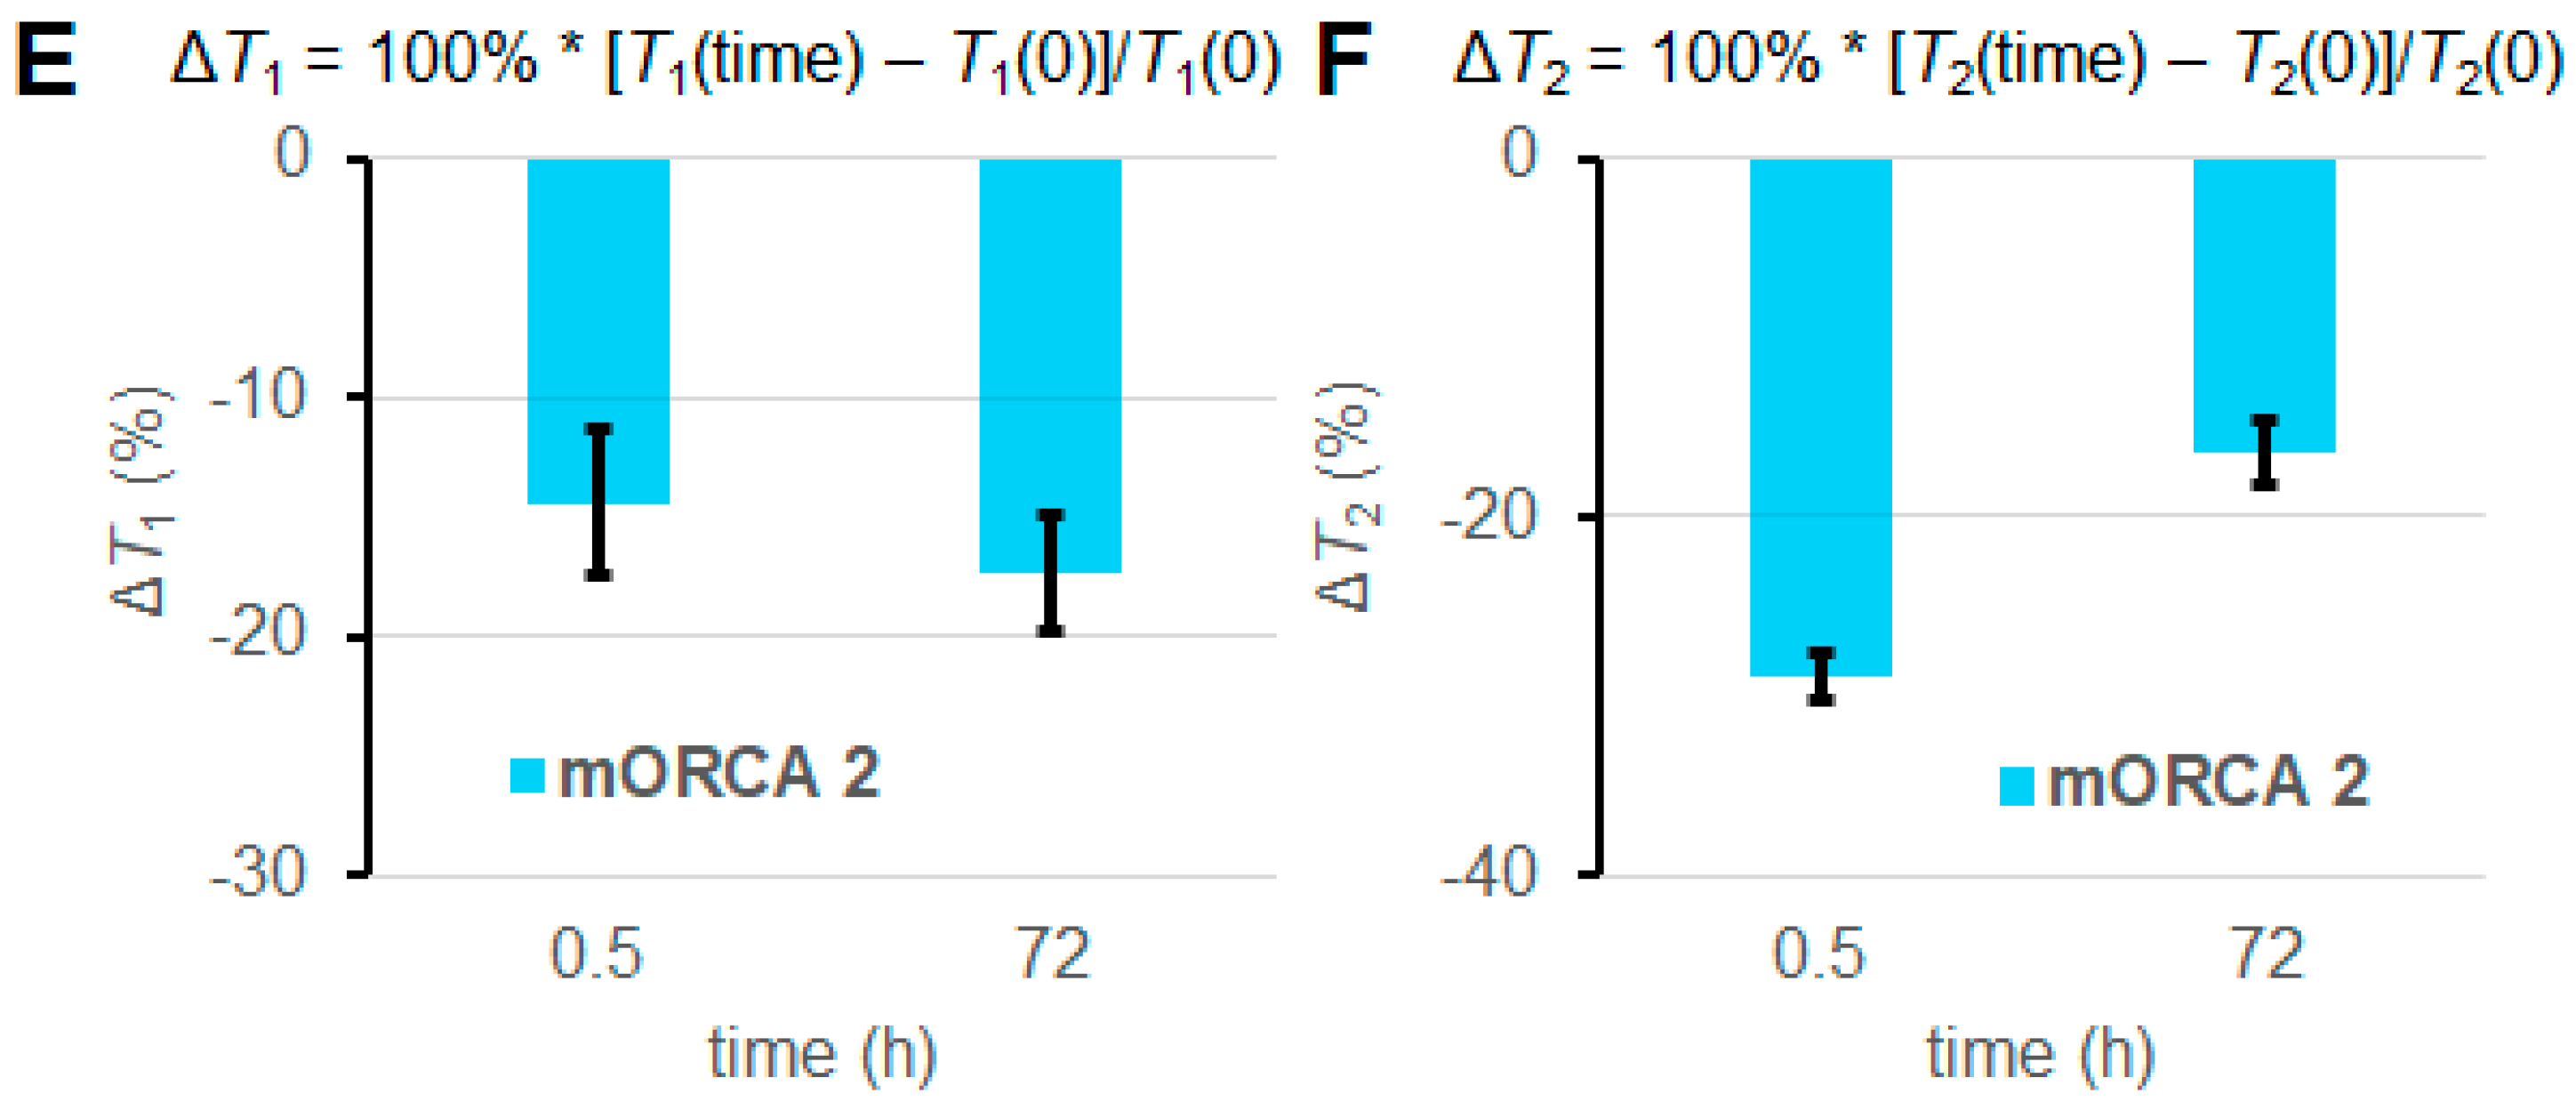

2.4. Ex Vivo EPR Spectroscopy of 1 and 2

| Tissue | n 1 | τcor (ns) 2 | Fast Component 2,3 |

|---|---|---|---|

| Blood | 7 | 4.0 ± 0.3 | 0.00 |

| Kidney | 10 | 6.0 ± 0.5 | 0.40 ± 0.06 |

| Liver | 4 | 9.2 ± 0.4 | 0.37 ± 0.05 |

| Lung | 4 | 5.5 ± 0.6 | 0.51 ± 0.03 |

| Brain | 1 | 3.9 | 0.73 |